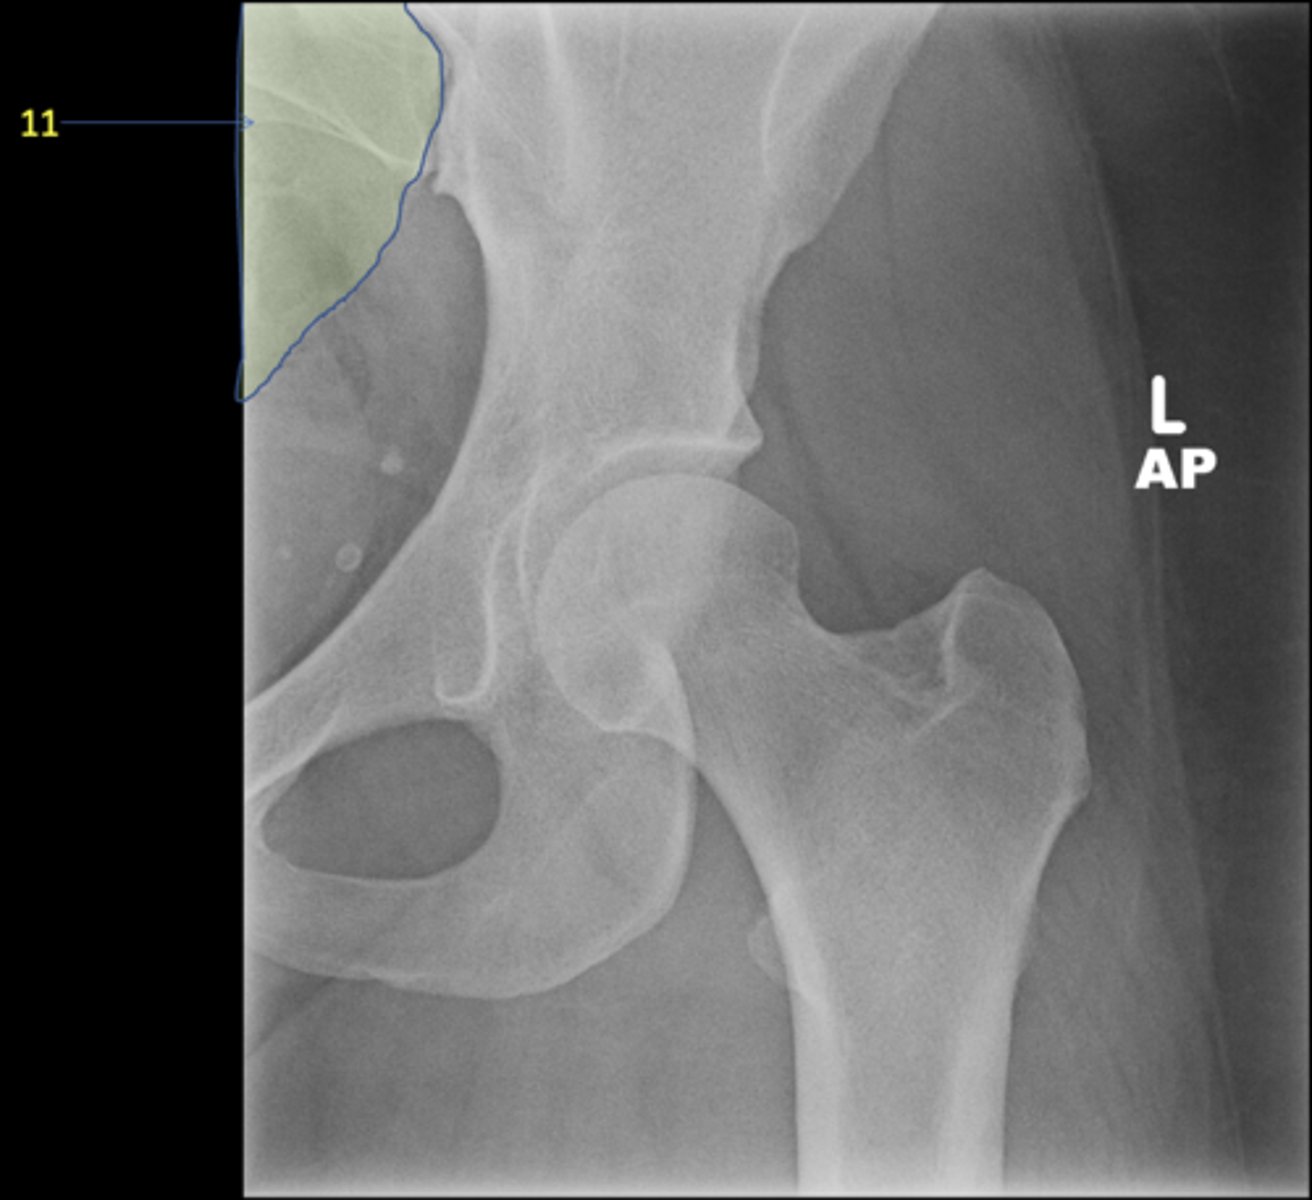

11

New cards

Right posterior superior iliac spine

ID 11

<p>ID 11</p>